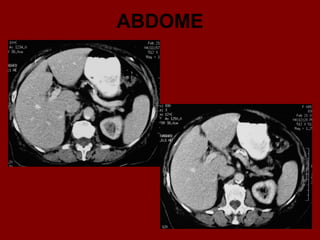

ABDOME